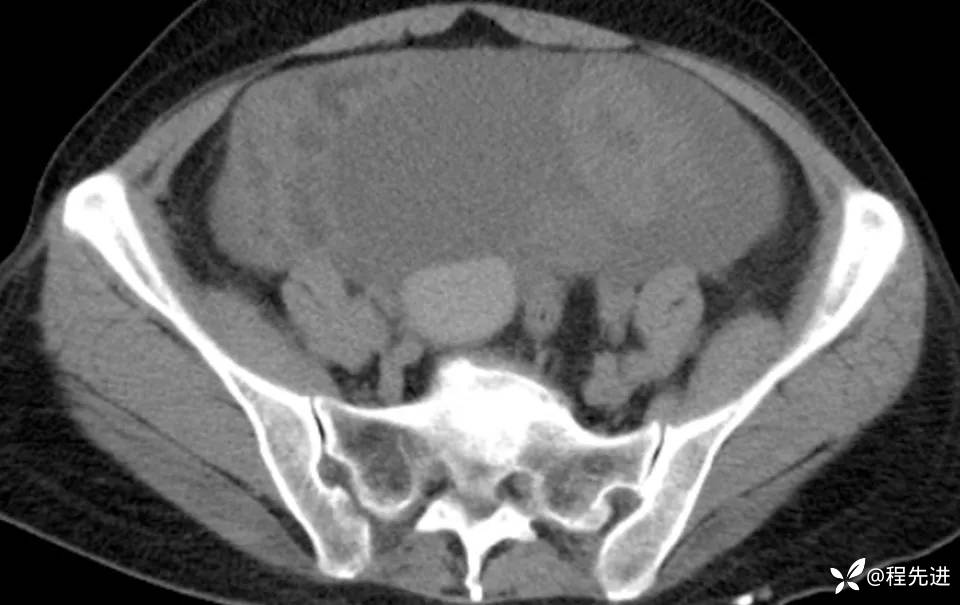

患者性别:女

患者年龄:56岁

简要病史:腹胀伴劳累性胸闷1月

肿标:CA125: 546.99U/ml;CA199: 269.9 U/ml,余未见异常

CT平扫+增强: